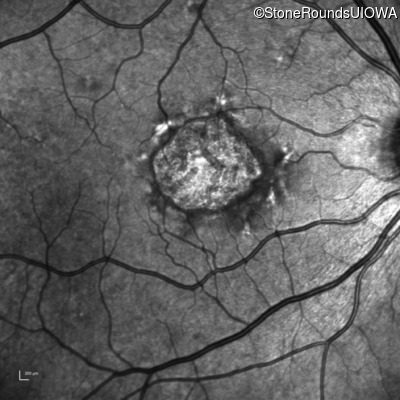

Infrared Fundus Photograph - Left - 20/160 -1 sc

Exemplar